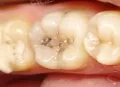

Наиболее распространен. Именно на этой стадии пациенты чаще всего и обращаются к врачу за помощью. На этой степени развития кариозная полость затрагивает не только зубную эмаль, но и дентин. Зуб становится чувствительным и реагирует болью не только на горячее или холодное, но и на прикосновение. Зачастую на этой стадии любой прием пищи превращается в болезненный процесс.

Были у стоматолога, врач поставил диагноз — кариес на задних коренных зубах в форме креста. А другой сказал, что все в порядке и это естественное потемнение в пространствах зуба от еды. Так как тогда определить?

• Скорее всего — это глубокий кариес. Обратитесь к врачу и немедленно лечите зубы. В противном случае скоро придётся удалять нервы.